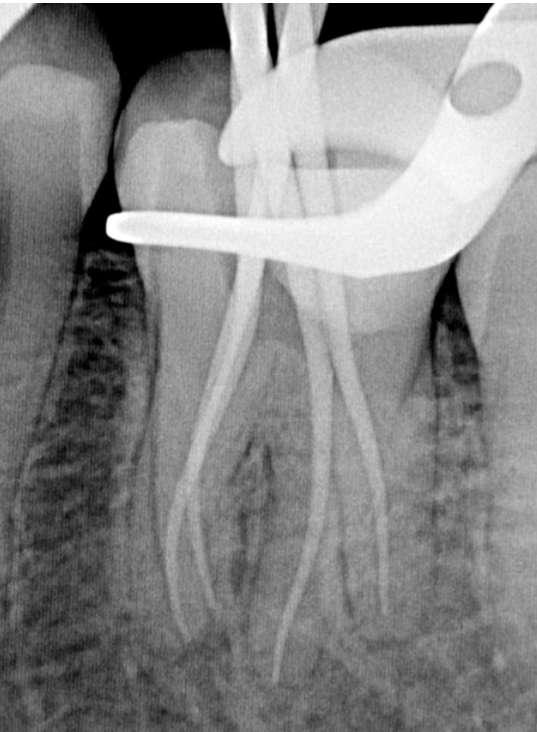

Die abschließende Spülung erfolgte zunächst eine Minute mit schallaktivierter EDTA-Lösung, gefolgt von einer Minute mit schallaktivierter NaOCl-Lösung. Das Wurzelkanalsystem wurde gespült, getrocknet und dann mit einer hydraulischen Single-Cone-Technik und einem biokeramischen Sealer (BUSA, BC Sealer) verschlossen. Zur Überprüfung der Behandlungsqualität wurden zwei periapikale Röntgenaufnahmen aus verschiedenen Winkeln angefertigt (Abb. 3-4).

Der Verdacht des Klinikers auf eine ungewöhnliche Anatomie der distalen Wurzel wurde durch das abgewinkelte Röntgenbild bestätigt, das eine abrupte versteckte Krümmung im apikalen Drittel des Kanals zeigte. Trotzdem ermöglichte der Crown-Down-Ansatz (zunächst Aufbereitung des koronalen und mittleren Teils, wodurch koronale Interferenzen reduziert werden) und die richtige Auswahl sehr flexibler und widerstandsfähiger

Abb.3 Abb.4